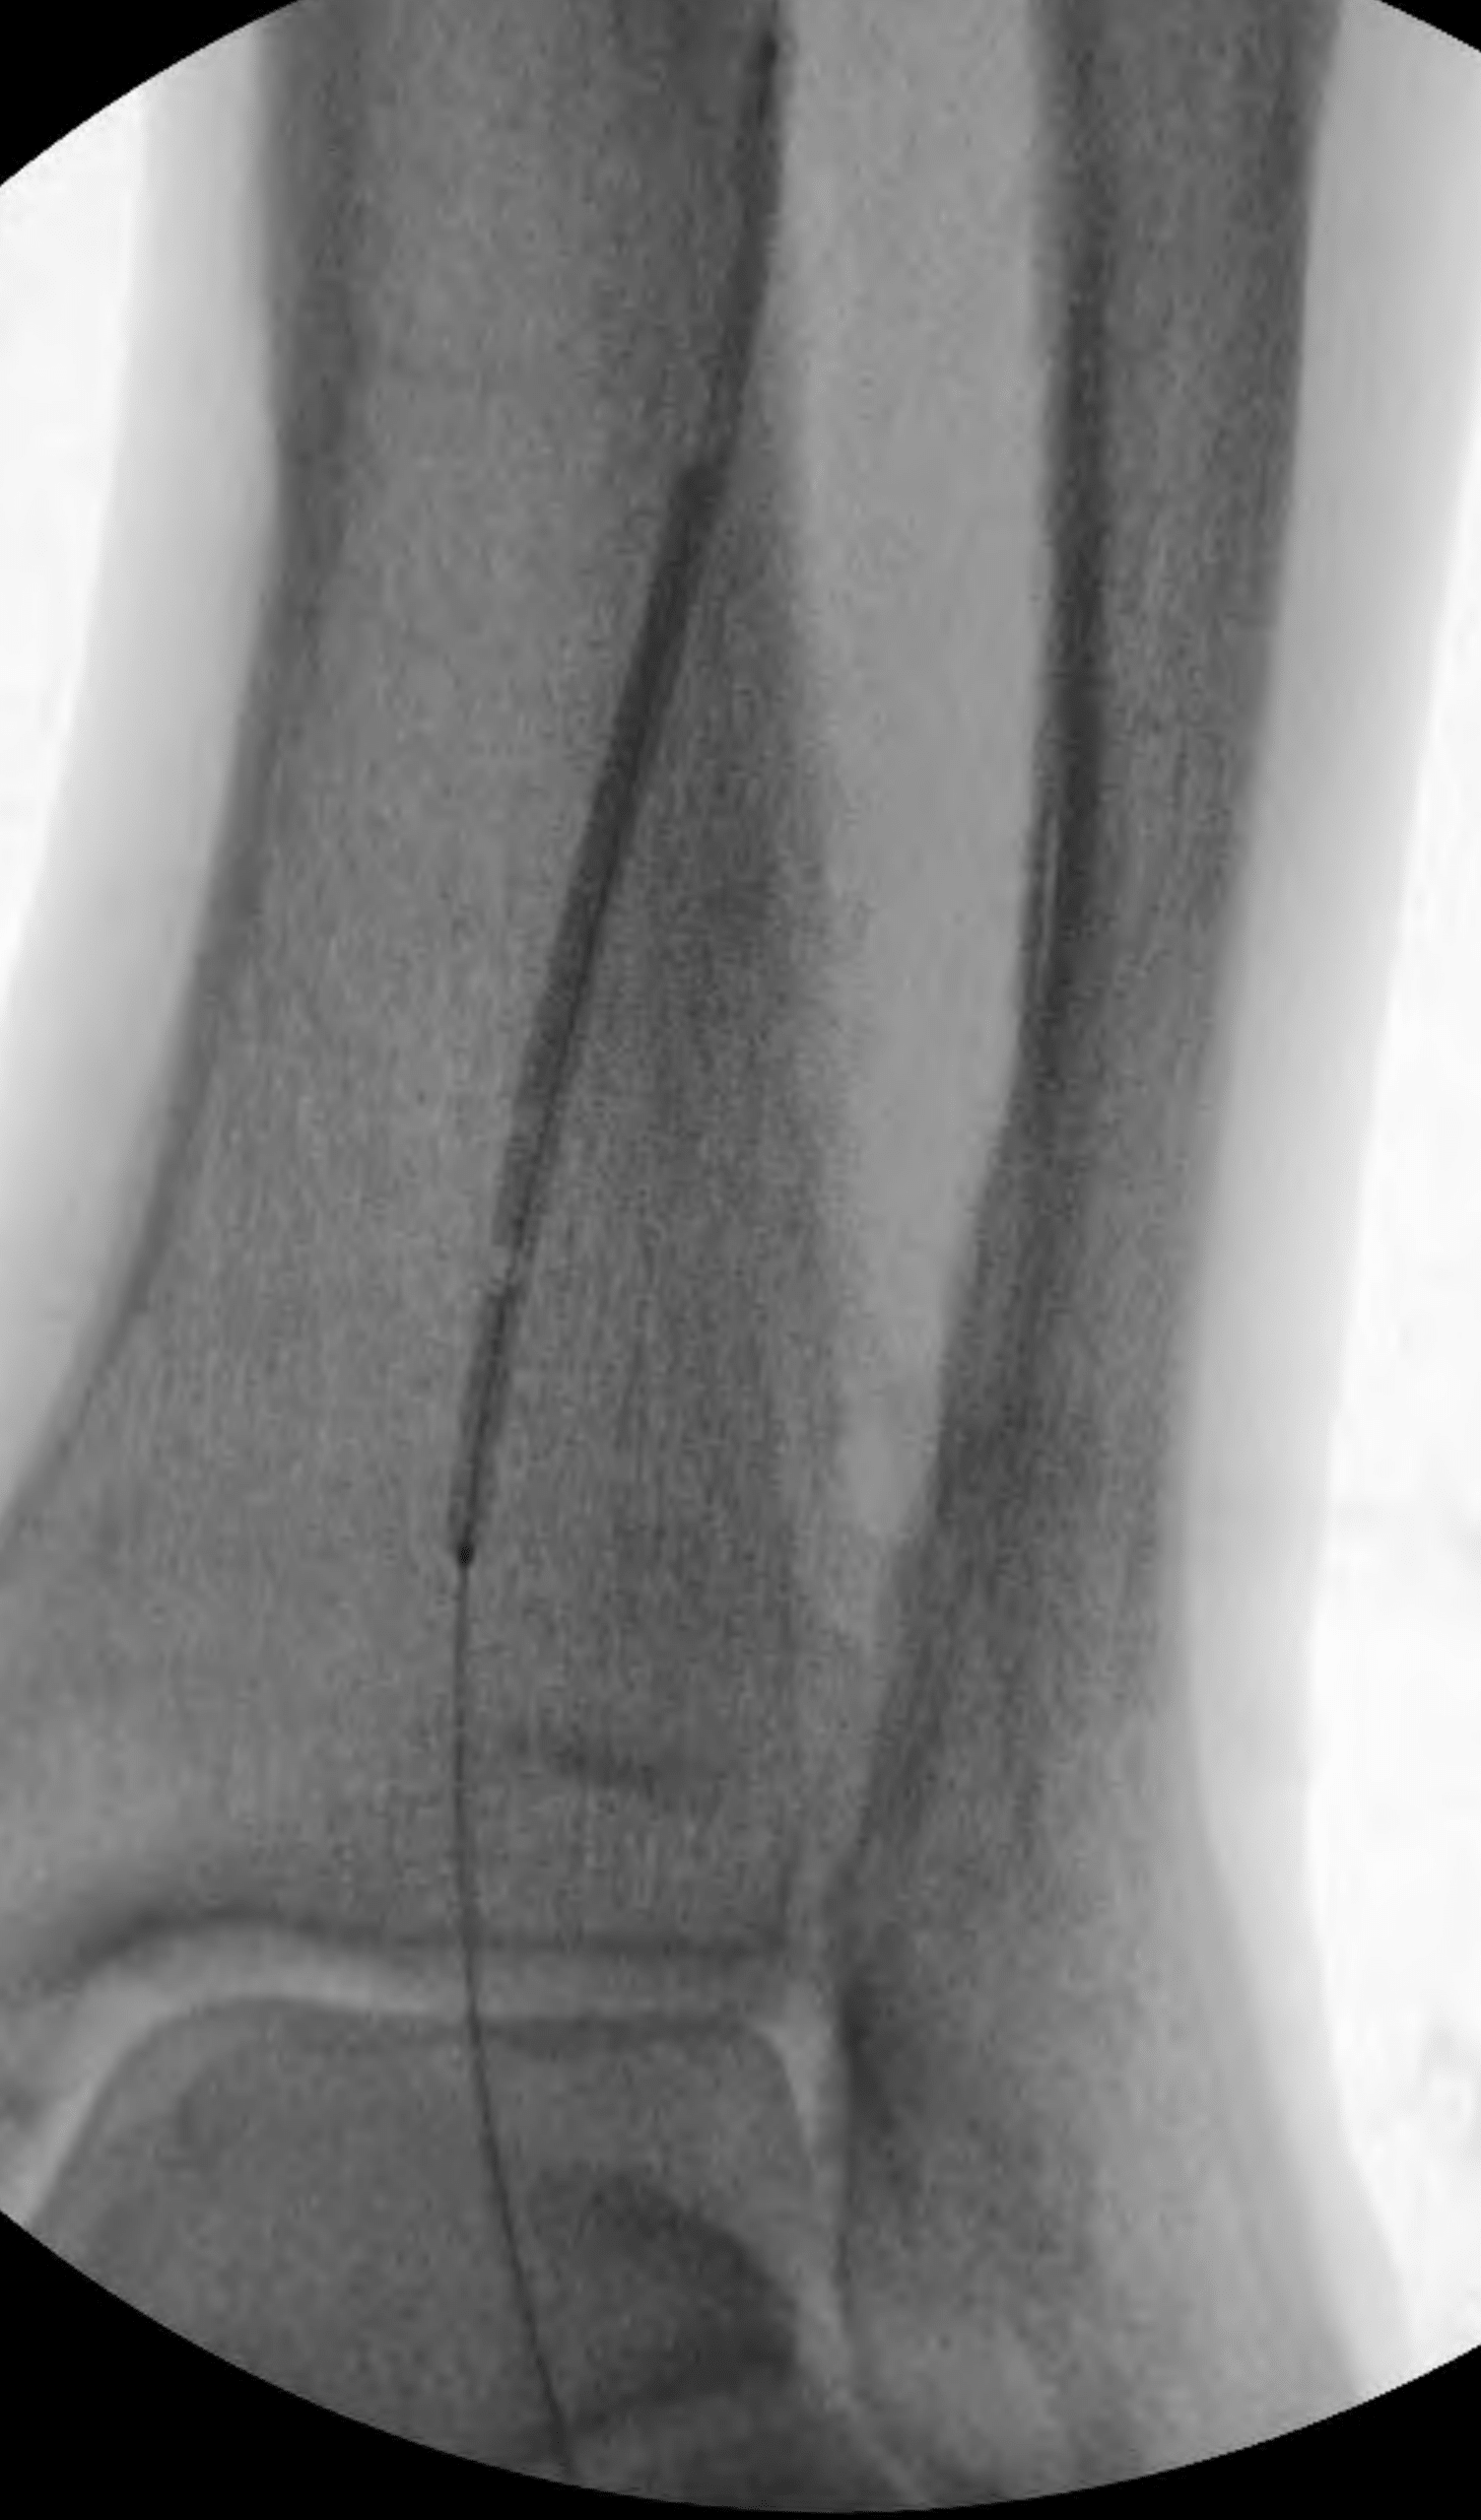

This allowed antegrade advancement of a wire from the “up and over” access into the further distal anterior tibial artery. However, it was still not possible to advance a catheter in antegrade fashion into the true lumen dorsalis pedis artery. Therefore, another retrograde access was obtained—this time, into the patent reconstituted dorsalis pedis artery (Figure 8).

The wire from this new access point was successfully advanced in retrograde fashion through the occlusion in the far distal anterior tibial artery into the more proximal true lumen of the anterior tibial artery. A 2-mm balloon was inserted “bareback” through this new access point, and angioplasty was performed across the far distal anterior tibial artery occlusion (Figure 9). The balloon was withdrawn.